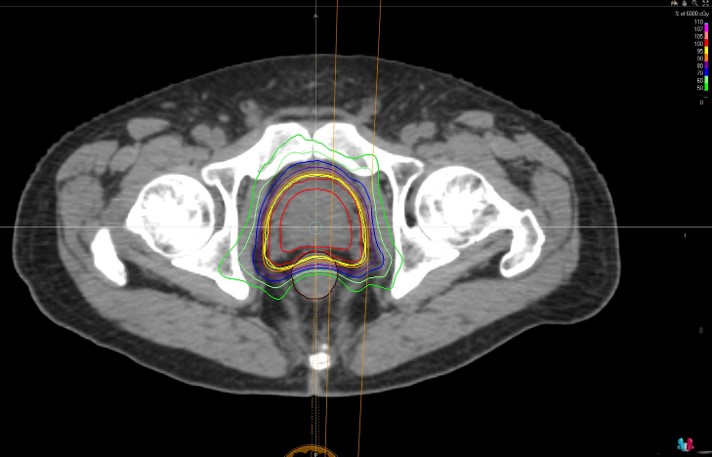

当院では、外照射療法をVMAT(強度変調回転放射線治療)で行っており、従来の外照射療法よりも直腸や膀胱など正常臓器への放射線を低減しつつ、前立腺癌により高い線量を照射することが可能になりました。

CTデータをもとに、前立腺への線量を最大化し、正常組織への影響を最小限に抑えるよう治療計画を立案します。

治療装置上で簡易的なCT(コーンビームCT)を撮影し、前立腺の位置を正確に確認してから照射を行います。

照射時は、直腸を空にし、膀胱に尿をためた状態にする必要があります。

治療は最大で20回(総線量60グレイ)で行い、1日1回、週5回の照射を毎日実施します。